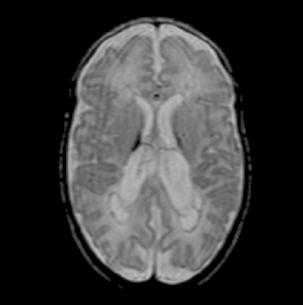

Kazuistika

Osmdesátiletá pacientka, z kardiologických důvodů dlouhodobě na warfarinu, hypertonička. Náhlé bezvědomí, pád z postele. Při přijetí somnolentní, jednoduchým výzvám vyhoví, hlavu a bulby stáčí doprava, levostrannými končetinami hůře pohybuje. Zemřela 5. den po mozkové příhodě.

Obr. A2.1–A2.4 Intracerebrální krvácení v akutním stadiu (1. den), oxyhemoglobin, ale již příměs deoxyhemoglobinu